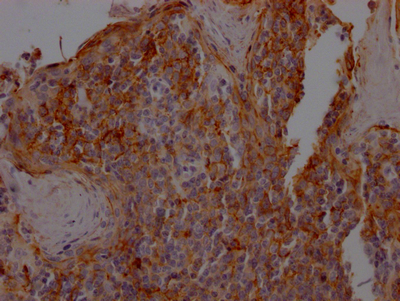

IHC image of CSB-RA162789A0HU diluted at 1:100 and staining in paraffin-embedded human tonsil tissue performed on a Leica BondTM system. After dewaxing and hydration, antigen retrieval was mediated by high pressure in a citrate buffer (pH 6.0). Section was blocked with 10% normal goat serum 30min at RT. Then primary antibody (1% BSA) was incubated at 4℃ overnight. The primary is detected by a Goat anti-rabbit IgG polymer labeled by HRP and visualized using 0.05% DAB.